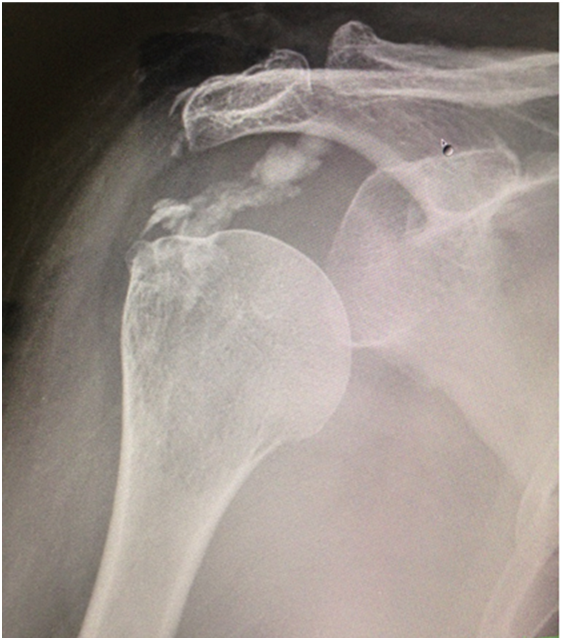

Figure 1 Preoperative radiographs (anteroposterior view) showing calcific deposits in the upper and anterior portion of the humerus.

A 50yr/Female with left upper limb monoplegia presented in outpatient department with complaints of pain in the right shoulder, with restricted movement of the right shoulder thereby affecting her activities of daily living, pain was sudden in onset present since last 3 months but was never shown to any physician since the intensity of pain was tolerable. On examination, the left upper limb had a power of Gr 0, Right shoulder there was wasting of the scapular and deltoid muscles. Tenderness was present on the right sterno clavicular joint, with flexion of 30 degree, abduction 20 degree and extension 10 degree. Drop arm sign positive, positive impingement sign, Test for subscapularis musculo tendinous belly press and lift off test was not possible. Blood test did reveal an uncontrolled Type II diabetes and echo showed a compromised cardiac status. Plain radiography showed a calcific deposit on the anterior and upper part of the humerus (Figure 1). Magnetic resonance imaging showed evidence of a calcific lesion in the supraspinatous tendon with evidence of partial tear of the rotator cuff (Figure 2). On the basis of these finding we made a diagnosis of calcific tendinitis of the supraspinatous tendon. The removal of the calcific tendon was challenging considering the disability of the patient, uncontrolled diabetes.